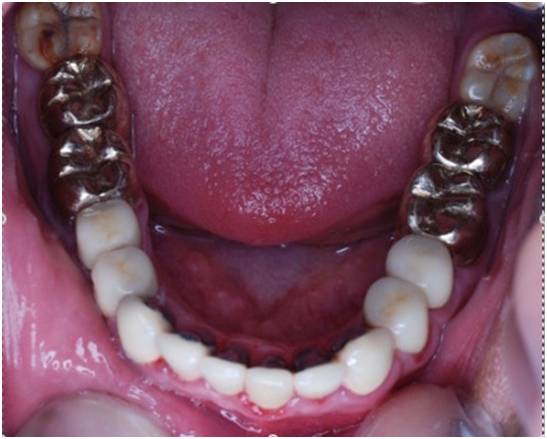

A 22 Yemeni male patient presented to the College of Dentistry clinics at the University of Dammam seeking cosmetic treatment with a chief complaint “I want to improve the way my teeth look " He reported no significant medical history. Patient has never been into the dental clinic. He stated his deciduas teeth were normal and his whole village complains of darkened teeth (brownish). A panoramic x-ray (Figure 1), intraoral pictures (Figures 2−6) as well as study casts were taken to diagnose the case (Figure 7). Upon examination, the patient was found to suffer from severely generalized discoloration of permanent teeth and moderate dental attrition resulting in shortening of the vertical dimension of occlusion (VDO). A class I occlusion with class I canine relation was present, with an over-bite of 4mm and an overjet of 4mm. The upper lip seems stretched with dropping mouth angles. The patient suffers from generalized marginal chronic gingivitis with no mobility or furcation involvement noticed. The treatment plan started with plaque control measures were conducted as well as patient education. The patient's esthetic problem caused by Fluorosis both teeth staining and facial appearance and occlusion. The treatment options available range from bleaching, porcelain veneers, full coverage ceramic crowns or porcelain fused to metal crowns. Due to the Fluorosis severity, the bond strength of the adhesive agent was questionable that eliminated the veneers option. Bleaching when tried had minimal effects. Finally, porcelain-fused to metal (PFM) crowns were selected to restore esthetics of anterior teeth, while posterior gold crowns were chosen to raise the occlusion posterior by 2mm. Treatment options were discussed with the patient who consents to the treatment plan.

Figure 4 Pre op lower arch.